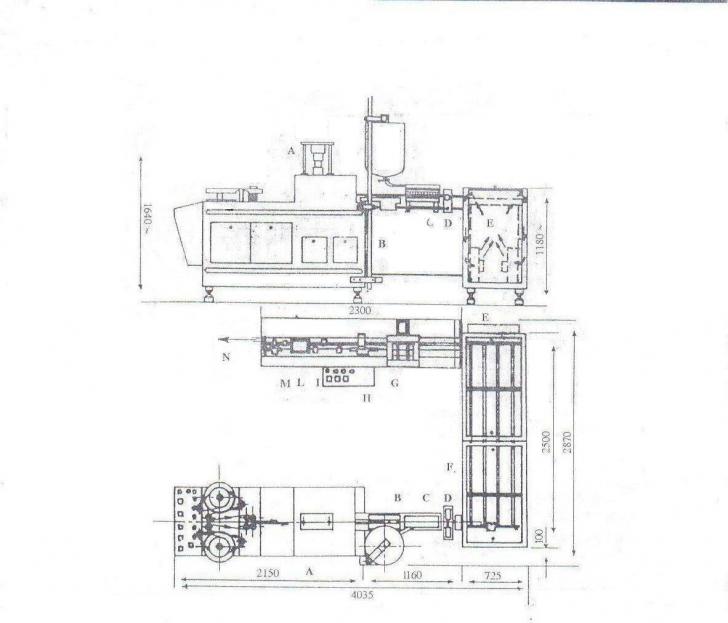

OVULE CU CLOTRIMAZOL 100mg

OVULE CU CLOTRIMAZOL 100mg 1. Formula de fabricatie Administrarea substantelor medicamentoase se face sub forma unor preparate farmaceutice convenabile administrarii pe anumite cai de administrare. Obiectivul formularii mCiteste tot ... 3408 cuvinte

Dimensiune medie

+ cu poze |